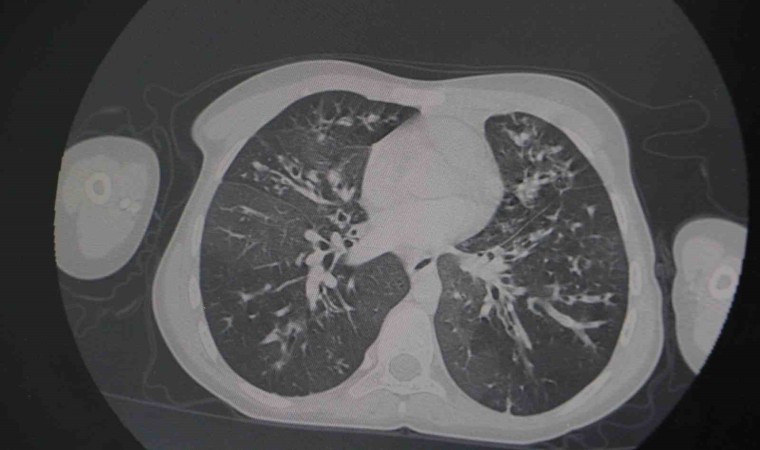

Kistik fibrozis hastalığının en sık akciğer tutulumu yapmakla birlikte mide-bağırsak sistemi ve pek çok sistemleri de tutabilen bir hastalık olduğunun altını çizen Meral, “Biz hastalara ne kadar erken tanı koyarsak bu hastalığın hem ilerlemesinin önüne geçmiş oluyoruz. Takibimizde olan hastaların da uygun şekilde tetkiklerini yaparak koruyucu önlemler alıp en ufak bir enfeksiyon durumunda erken müdahale ederek akciğer hasarının da önüne geçmiş oluyoruz” ifadelerine yer verdi.

Hastaların belirli aralıklarla mutlaka takiplerinin yapılması, uygun şekilde örneklemelerin alınmasının çok önemli olduğunu dile getiren Meral, “Bu aşamada belirli aralıklarla görüntüleme yapıyoruz. Hastaların örneklemelerini alıyoruz. Burada bizim için önemli olan hastaların balgam tahlillerini yapabilmek. Bu tahliller neticesinde enfeksiyonlar olabilir. Bu hasta grubunun en önemli sorunu zaten dirençli enfeksiyonlar olmasıdır. Bu dirençli enfeksiyonlar için erken dönemde tedaviye başladığımız zaman daha da direnç kazanmasının önüne geçmiş oluyoruz. Bu nedenle bu hastaların belirli aralıklarla mutlaka takiplerinin yapılması, uygun şekilde örneklemelerin alınması önemlidir. Biz de zaten hastanemizde bu hastalarımızın takibi için ayrı bir oda ve birim oluşturduk” diye konuştu.